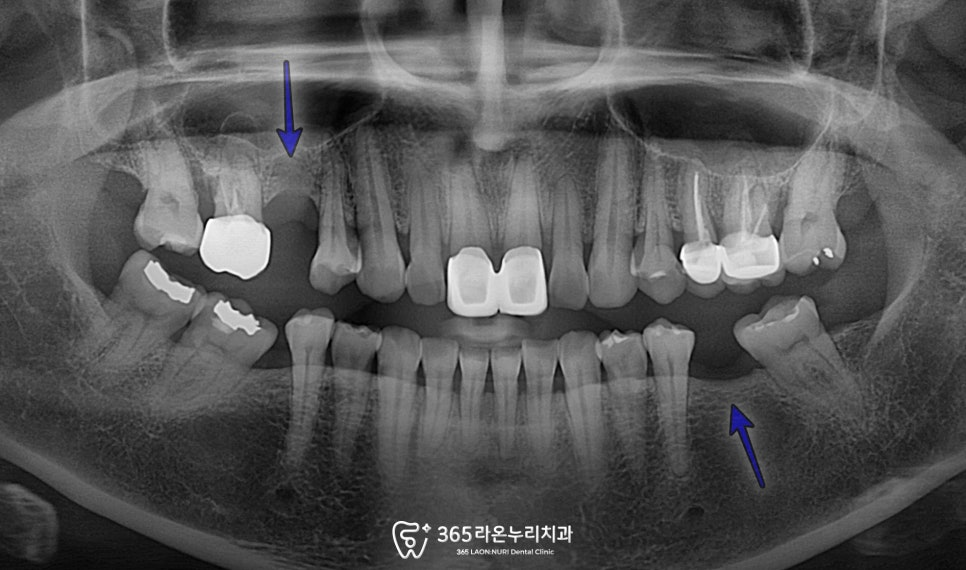

오산대역 치과 에서

초진 파노라마 엑스레이를

확인해 보면

비어있는 치아들을 쉽게 찾을 수 있습니다.

게다가 치조골이 조금씩 내려가고 있고,

다행히 대합치 정출이나 않았기에

해당 문제가 나타나기 전, 빠르게

채워 넣어주는 것이 필요할 듯 합니다.